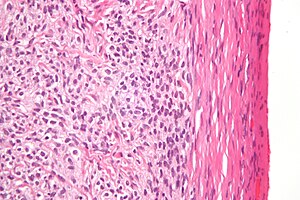

Thecoma. H&E stain. | |

| LM | bland oval or spindled nuclei, abundant cytoplasm that is pale and vaculolated |

| LM DDx | ovarian fibroma, fibroma-thecoma |

| IHC | alpha-inhibin +ve |

| Gross | solid yellow mass, usually well-circumscribed |

Thecoma is an ovarian sex-cord stromal tumour.

- Nuclei with oval to spindle morphology.

- Abundant cytoplasm that is pale, vaculolated -- key feature.